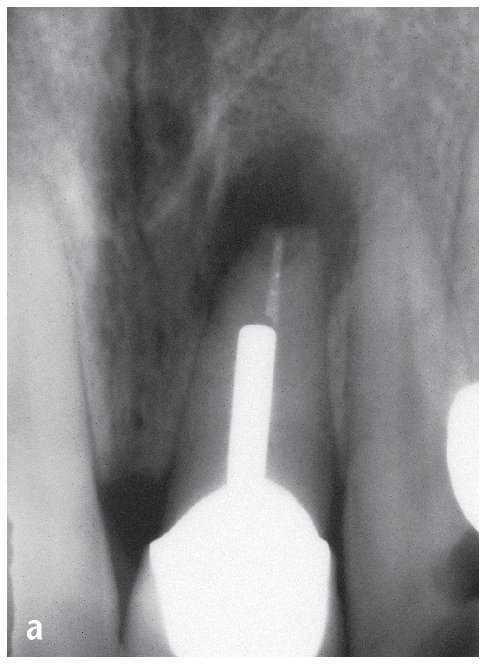

Figura 1a. Radiografía diagnóstica ortorradial del diente 43: una imagen radioopaca «interrumpe» el conducto radicular en el tercio medio de la raíz, fuerte curvatura apical del conducto radicular hacia mesial.

Figura 1b. En el segmento coronal de la raíz se observan dos conductos radiculares orientados en sentido vestibulolingual que están unidos por un istmo.

Figura 1c. En la proyección excéntrica de la conductometría se aprecia claramente la configuración tipo VI de Vertucci: los dos conductos radiculares están separados por un septo en el tercio medio y se unen nuevamente por debajo de éste mediante un istmo en el que se encuentran todavía restos de CaOH de la primera sesión. Los dos conductos muestran una trayectoria divergente en sentido apical para acabar en un foramen apical cada uno.